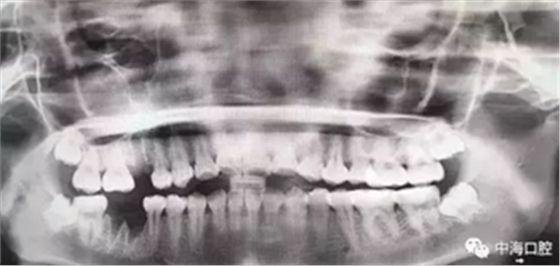

再比如智齒:

由于智齒的生長位置特殊,導(dǎo)致了拔除難易不同,如智齒出現(xiàn)橫著長或者靠近牙神經(jīng)的話,則難度會較高,一般人只需拍個口腔全景片,但相對于智齒靠近神經(jīng)管的情況,還可能需要拍CT,這都很考驗(yàn)牙醫(yī)的技術(shù)。